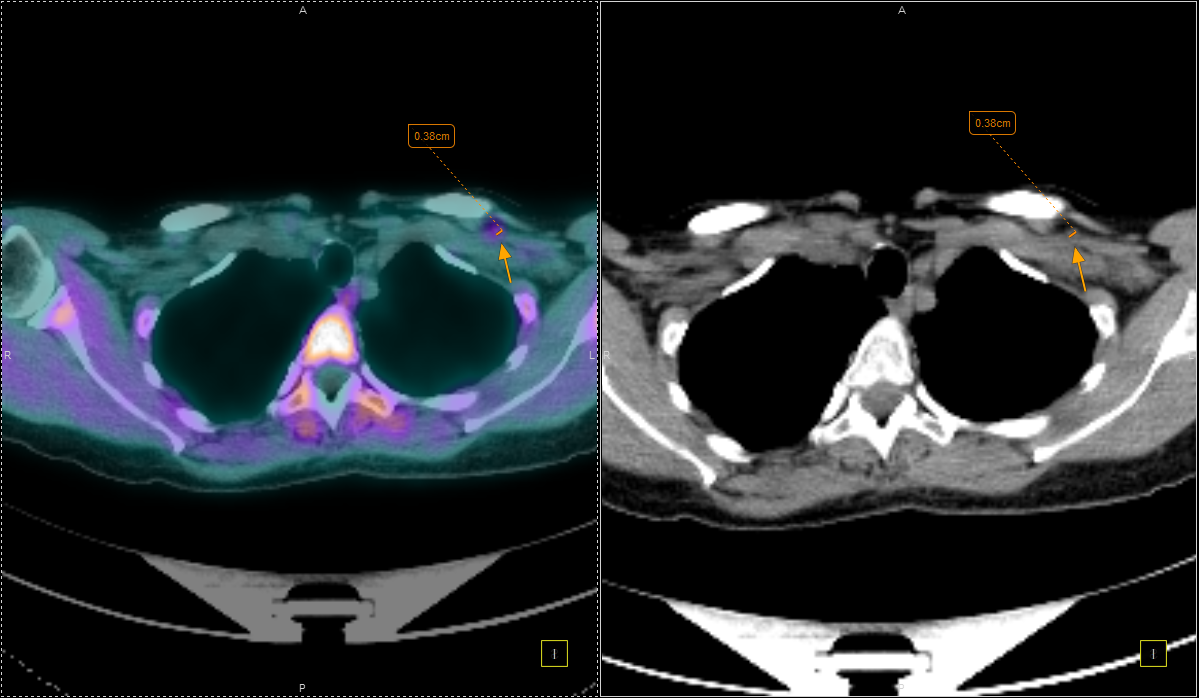

Με τη χρήση ειδικού λογισμικού Τεχνητής Νοημοσύνης (MIM – Lesion ID) πραγματοποιείται αυτόματος υπολογισμός της έκτασης και του όγκου των θέσεων ενεργού νόσου. Ξεπερνώντας τις δυνατότητες του ανθρώπινου οφθαλμού υπολογίζεται το συνολικό φορτίο νόσου πριν και μετά την θεραπεία επιτρέποντας ακριβέστερο χειρισμό του ασθενούς από τον θεράποντα ιατρό.